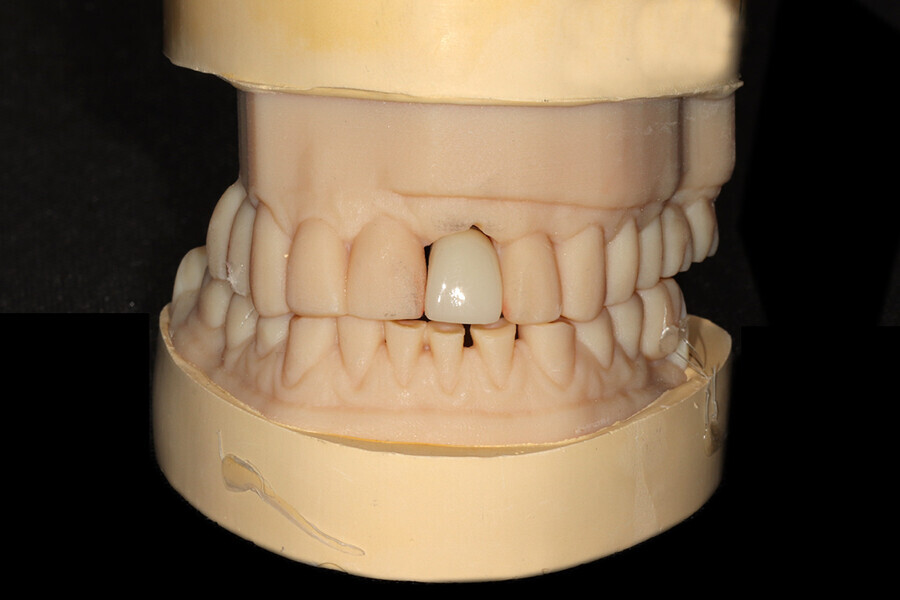

Fig. 1: The patient presented with a horizontally fractured clinical crown, an indication for a partial extraction therapy procedure.